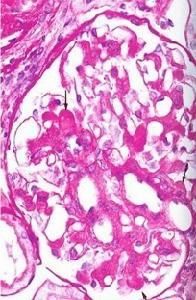

IgA腎炎病理圖檢查:

鏡下血尿者,尿紅細胞以畸形者為主。約50%患者血清IgA增高,但與病情活動無關。血清IgA中λ輕鏈濃度增高。尿免疫球蛋白測定無特殊意義。血補體成分大多正常。某些補體成分或因子可能減少,主要見於有家族高發傾向病人中,但不具有診斷價值。約半數病人IgA-纖維連線蛋白聚集物測定值可有一過性增高,雖然有助於與其他腎病鑑別但其與IgA腎炎活動無關,故並無診斷價值10%~15%病人可有IgA循環免疫複合物增高,32%病人有IgA類風濕因子水平增高多項免疫學指標,包括病毒和食物抗原、抗體、T細胞亞群、HLA位點抗原等測定結果可有改變,但均無診斷價值。50%病人前臂掌側皮膚活檢中可見毛細血管內有IgA和C3等沉積。